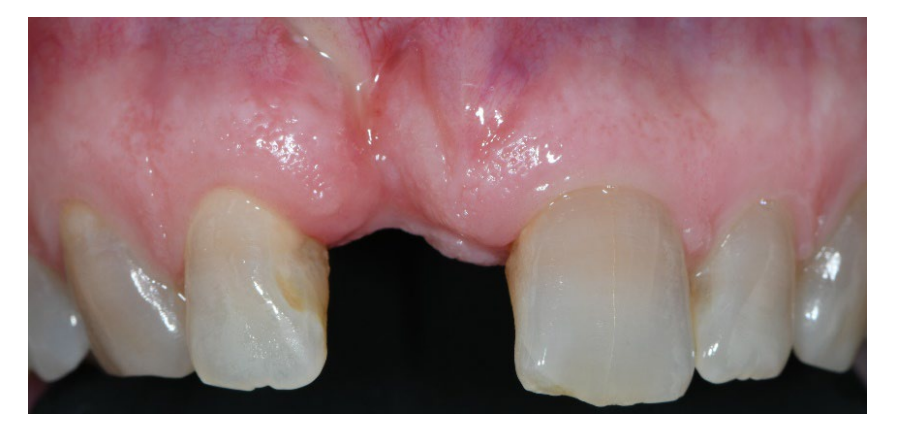

In both groups, six to eight months after tooth extraction (group A and B, respectively), dental implants (Premium, Sweden and Martina, Due Carrare, PD, Italy) were placed. In none of the cases was it necessary to carry out an additional GBR. The amount of bone was judged sufficient to place an implant of 3.8 mm of diameter and 10 to 11.5 mm of length. Flap design was performed according to the clinical scenario and the patient’s requirements. Before implant site preparation, a calibrated trephine bur with a 3.0 mm external diameter was used to collect a core sample for histologic analysis. The implants were submerged for three months. Three months after implant placement, a screw-retained temporary restoration was delivered. Finally, two to three months after initial loading, a definitive, screw-retained, CAD/CAM, metal-free restoration was delivered. Occlusion was adjusted, and follow-up visits were scheduled every four months.

No implant failure and no complications were experienced. In addition, all the patients were fully satisfied with the function and aesthetic of their implant-supported restoration, and no differences were experienced in their perception of the therapy, so all the patients would undergo the same therapy.